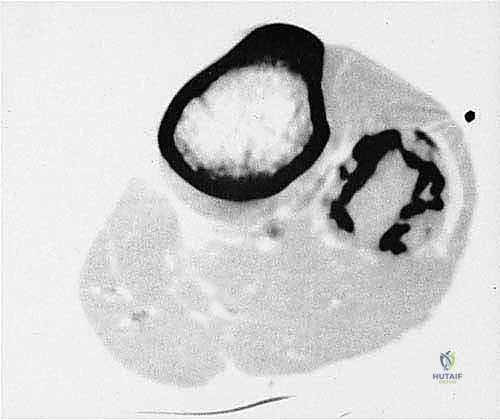

- التصوير بالرنين المغناطيسي (MRI): المعيار الذهبي. يوضح بدقة متناهية امتداد الورم داخل نخاع العظم، وحجم الكتلة في الأنسجة الرخوة المحيطة، وعلاقة الورم بالأعصاب والأوعية الدموية.

- التصوير المقطعي المحوسب (CT Scan): ممتاز لتقييم التفاصيل الدقيقة للقشرة العظمية واكتشاف أي تكلسات داخل الورم.

- العصب الشظوي الشائع (Common Peroneal Nerve): هذا العصب هو الهاجس الأكبر لأي جراح أورام عظام. ينشأ من العصب الوركي ويتجه سطحيًا ليلتف حول عنق الشظية (أسفل رأس الشظية مباشرة). أي إصابة، أو شد، أو قطع لهذا العصب أثناء إزالة الورم ستؤدي فوراً إلى حالة تُعرف بـ "سقوط القدم" (Drop Foot)، حيث يفقد المريض القدرة على رفع قدمه للأعلى، مما يؤدي إلى تعثر دائم أثناء المشي، بالإضافة إلى فقدان الإحساس في الجزء العلوي والخارجي من القدم.

- الأوعية الدموية المأبضية (Popliteal Vessels): تقع الشرايين والأوردة المأبضية خلف الركبة، قريباً جداً من الجزء العلوي للشظية.

- الشريان الظنبوبي الأمامي (Anterior Tibial Artery): يمر هذا الشريان الحيوي مباشرة إلى الأمام عبر فتحة في الحاجز بين العظمين (Interosseous membrane) الملاصق للشظية.

- الشريان الشظوي (Peroneal Artery): يسير هذا الشريان بمحاذاة السطح الخلفي للشظية ويغذي العضلات المحيطة بها.